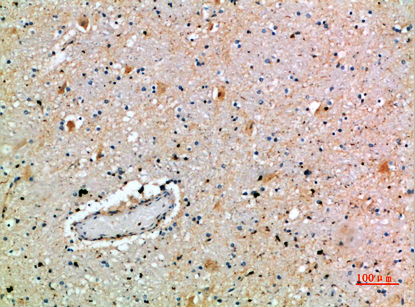

分类: 科研抗体货号: P43512别名: Collagen alpha-1(I) chain (Alpha-1 type I collagen)应用: IHC反应种属: Human,Mouse,Rat